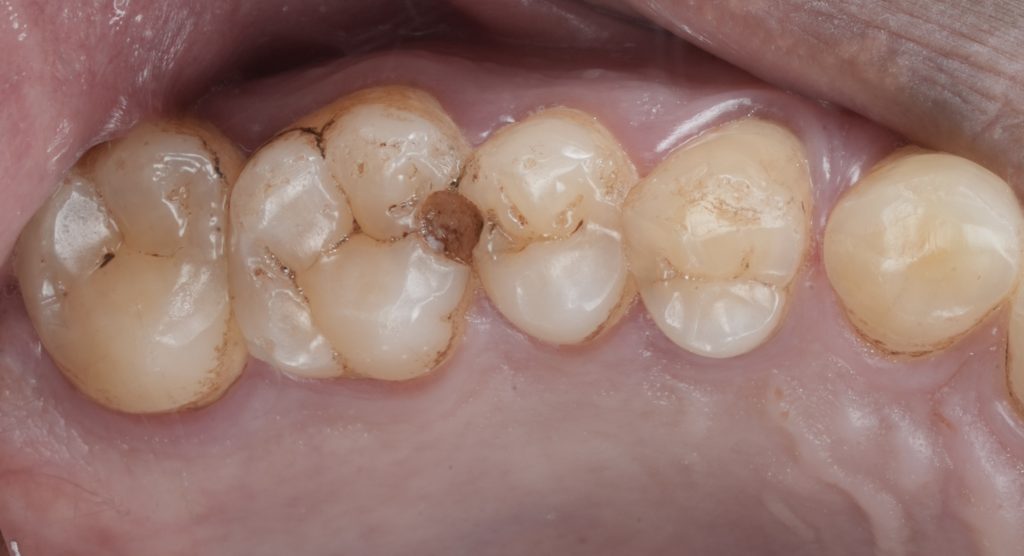

The final restoration demonstrated:

- Tight, anatomically correct proximal contact

- Smooth marginal adaptation

- Preserved pulp vitality

- Natural contour consistent with adjacent teeth

The patient reported immediate comfort with no post-operative sensitivity.

Predictable Class II restorations are not achieved by chance. They are the outcome of discipline, visibility, and respect for tooth biology.

By prioritising isolation, controlled proximal contouring, and conservative adhesive techniques, vital posterior teeth can be restored with longevity, comfort, and functional success.